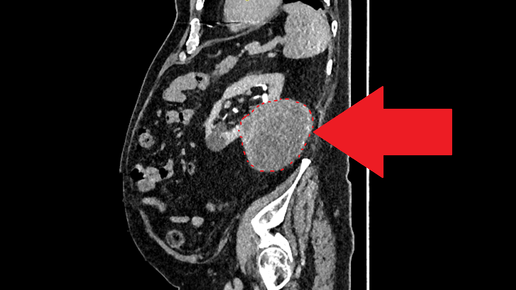

Учёные проверили препарат и на более реалистичных моделях. На доклинических моделях с человеческими клетками аденокарциномы легких инъекции AVJ16 почти полностью останавливают рост опухолей и метастазы.